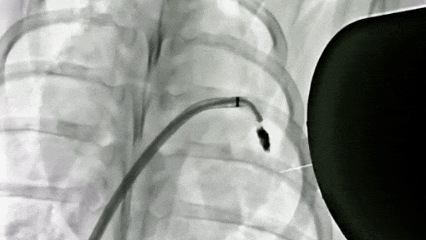

DSA(数字减影血管造影)拍摄的巴马猪体内磁流体左心耳封堵实验过程。深圳先进院供图